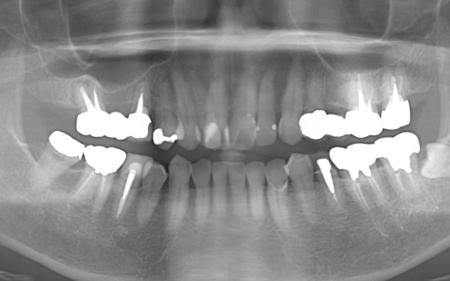

50代男性 バランスが崩れた噛み合わせをインプラント治療と被せ物治療で改善した症例

- 骨再生

- 詰め物・被せもの

- セラミック・ジルコニア

- インプラント

- サイナスリフト

- 治療期間の目安 3年

- 治療回数の目安 約45〜50回

約4,479,545円

【内訳】

サイナスリフト、骨移植、インプラント6本、他院インプラント人工歯作り替え、ジルコニアクラウン(インプラント人工歯6本、被せ物3本)、ダイレクトボンディング

治療のリスク

・外科手術のため、術後に痛みや腫れ、違和感を伴います ・メンテナンスを怠ったり、喫煙したりすると、お口の中に大きな悪影響を及ぼし、インプラント周囲炎等にかかる可能性があります ・糖尿病、肝硬変、心臓病などの持病をお持ちの場合、インプラント治療ができない可能性があります ・高血圧、貧血・不整脈な...